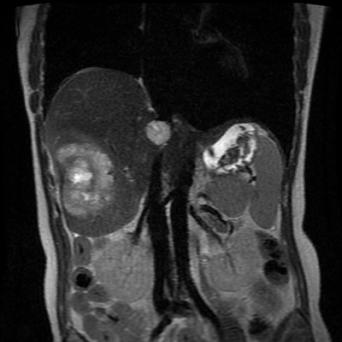

La stéatopathie métabolique est devenue la première cause de maladie chronique du foie. Le risque principal est la fibrose, qui, lorsqu’elle est sévère, peut évoluer vers une cirrhose et un carcinome hépatocellulaire. Qui faut-il dépister en soins primaires et comment interpréter les résultats ? Quelles options thérapeutiques ont fait leurs preuves ? Que peut-on attendre des nouvelles molécules ? Le point avec le Pr Stanislas Pol, hépatologue, hôpital Cochin, Paris.